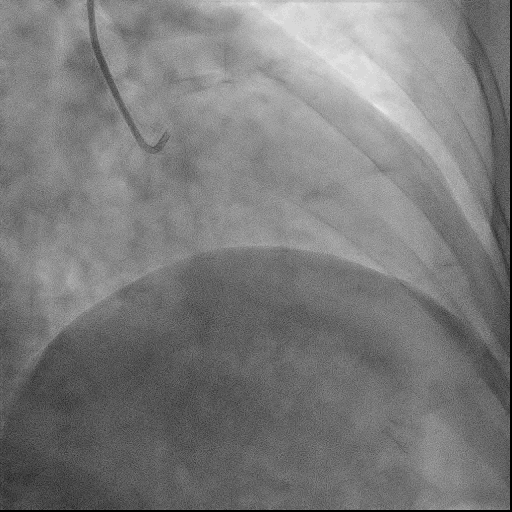

葛雷教授手术现场

术前冠脉造影

RCA近中段弥漫性狭窄伴钙化,狭窄30-60%,RCA远端发出广泛侧支供应LAD远端